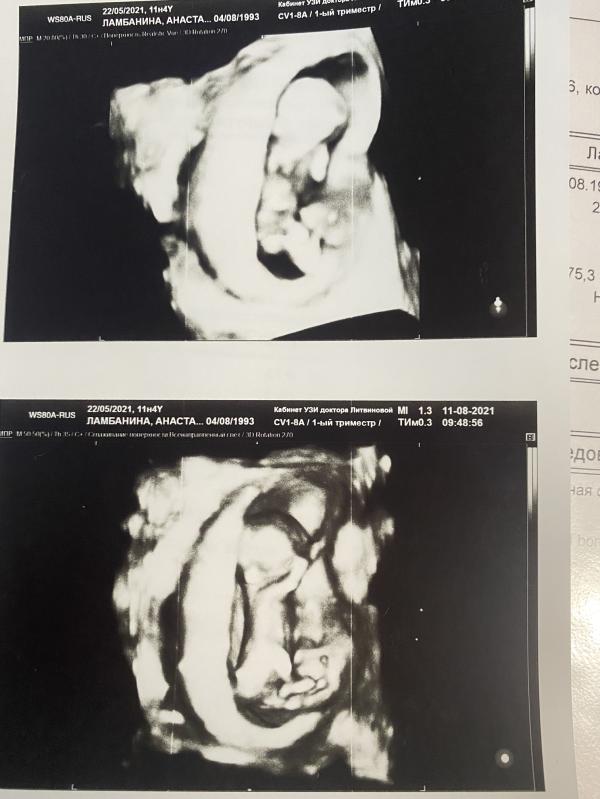

👶Пол- мальчик, узнали на узи 11.08.21

🐥Срок на момент родов - 35,6недель по ПДР, по первому узи 36,5 недель